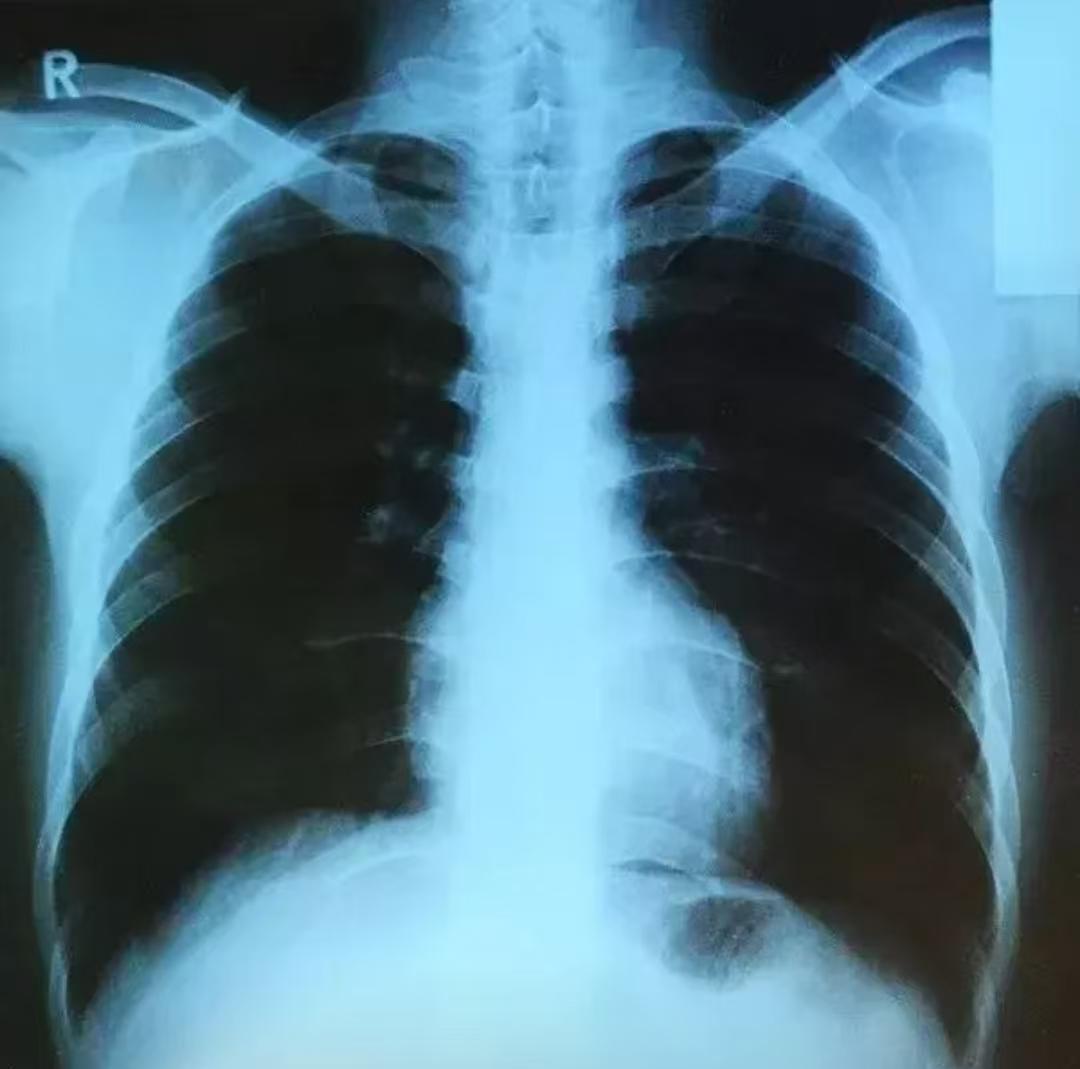

这件事我强调过很多次:肺结节长得越多,反而越要谨慎,不能轻易“一刀切”。 之前有位患者,47岁,两肺大大小小结节加起来有20多个,有些特别小,不仔细看CT都难发现。他在我这里定期随访,一跟就是五年多,直到最近才决定手术。 为什么能观察这么久?因为刚发现时,如果把所有怀疑是肿瘤的结节都切掉,切除范围会非常大,肺组织损失过多,肯定影响肺功能。 而经过三个月、半年、一年多次复查,这些结节一直很稳定,没有长大或变多,说明它们要么是“惰性”的,要么根本不长。这种情况,定期观察就是最安全的选择。即便未来有微小变化,再手术也完全来得及。 那为什么最近又决定手术了呢?是因为在最近一次复查中,发现其中一个结节的密度增高、变实了——这是一个“生长信号”,说明它开始活跃了,必须处理。 手术时我们也做了讨论和研究:既然要做,就尽量把同侧所有可疑的结节一次性处理干净。这样既能避免将来另一批结节出问题、患者又要挨一刀,也减少反复手术对肺功能的累积影响。 尽可能保护肺功能,我们设计了“肺段切除+楔形切除”的组合方案,一次手术切除了14个结节。术后病理显示,这些结节类型多样,从不典型增生、原位癌到微浸润、浸润癌都有。这也印证了他的多发性结节不是转移,而是多源发生的,各自独立生长。 至于另一侧剩下的结节,我建议继续定期复查。治疗一定要权衡利弊,在合适的时机做合适的决定。只要结节稳定,就不必积极手术;但如果哪天有变化,同侧也要争取一次处理到位。 医生的决策必须从患者实际情况出发,用最小的代价,争取最好的结果。[谢谢][玫瑰]胸外科乔贵宾医生肺结节[超话]